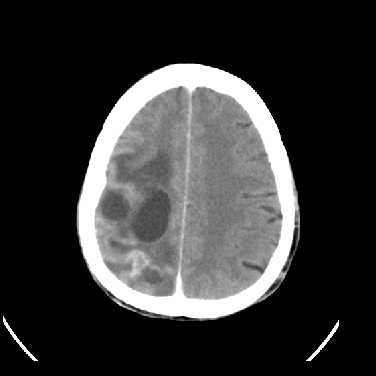

男,45岁,左侧肢体乏力1周。ex:胸片示:两肺团块状、斑片状密度增高影,其内可见小空洞。支纤镜、经皮肺穿示:干酪样物。

结合病史考虑结核性脑炎脑膜炎,伴脑脓肿形成

考虑右侧顶叶脑脓肿形成。

同意“考虑结核性脑炎脑膜炎,伴脑脓肿形成”的意见,不轻易怀疑肿瘤。

考虑结核性脑炎脑膜炎,伴脑脓肿形成。

考虑右侧顶叶脑脓肿(结核性?)。

结核性脑脓肿可能大

结合病史考虑结核性脑炎脑膜炎,伴脑脓肿形成,囊变转移瘤不除外